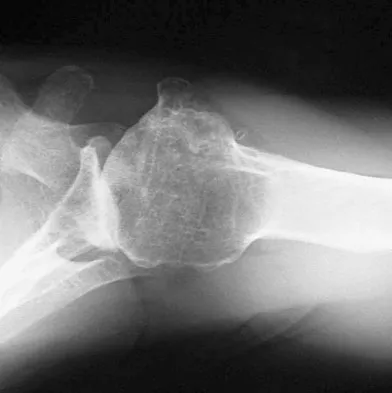

Figures 9a and 9b show the radiographs of a 12-year-old girl who has had right hip pain for the past 4 months. She reports that the pain is so severe that she is unable to walk and is now using a wheelchair. Examination reveals pain with any attempted range of motion. Management should include

Explanation

In addition to mild hip dysplasia, the radiograph shows an osteoblastic lesion of the right ilium. The patient's symptoms are much more severe than is typical for late hip dysplasia. MRI can determine the extent of the lesion in the bone and soft tissues. Following work-up and biopsy, the patient was diagnosed with Ewing's sarcoma. Springfield DS, Gebhardt MC: Bone and soft tissue tumors, in Morrissy RT, Weinstein SL (eds): Lovell and Winter's Pediatric Orthopaedics, ed 5. Philadelphia, PA, Lippincott Williams and Wilkins, 2001, pp 507-518, 542-544.